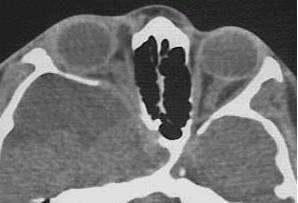

What type of image is it? CT scans or MRI scans (T1 or T2

weighted)

Which plane the image is in? axial, sagittal or coronal.

space occupying lesion in the orbit: lacrimal

fossa (lacrimal gland tumour)? intraconal lesion (optic glioma, capillary

haemangioma or optic nerve meningioma)? diffuse lesion (lymphoma, metastatic

tumour or acute infection or inflammation)? dilated superior ophthalmic

vein (carotid-cavernous fistula)?

bony lesion: localized bony expansion (meningioma

and osteoma in which the lesions have the same density as the surrounding

bone; fibrous dysplasia in which the bone density is reduced)? any bony

thinning next to an orbital lesion (suggesting long-standing chronic lesion)?

any lytic lesion (suggesting malignant lesions such as metastasis or myeloma)?